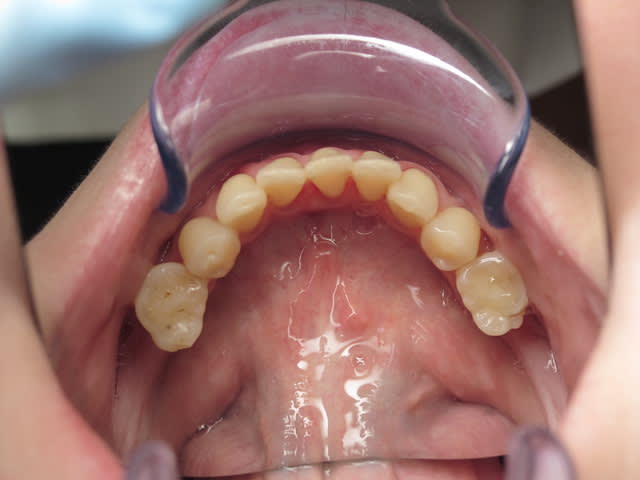

Patiente de 33 ans, questionnaire de santé RAS, demande esthétique. Elle souhaiterait que ses dents soient "davantage visibles" lors du sourire. Les dents absentes sont dues à des agénésies.

Il y a agénésies de 14-15 et 24-25, de 35 et 45 (restent 75 et 85), des molaires du bas. En haut j'avoue que je ne sais pas si ce sont des molaires de lait ou définitives...

Perso, je proposerai de faire une solution de compromis plus light, avec génioplastie, rhinoplastie pour tricher et "décreuser" le profil, prévoir des implants en "7" en bas (et les pseudo-6 quand elles tomberont... plus tard), et revoir le secteur antérieur ( c'est quoi ces cacas composites sur 12, 11 et 21?)avec juste peut être un éclaircissement, pour un effet trompe-l'oeuil.

perso, ca me fait un peu alluciner la sévérité de vos propositions; d'après la seule photo, je ne dirais pas que la patiente ait un menton vraiiiiiiment en galoche, elle vient juste pour une petite (je maintiens) demande esthétique, pas pour un extreme makeover acec psychanalyse à la clef (qui a dit qu'elle nétait pas bien? elle a le droit que pas etre satisfaite de son sourire sans etre depressive!) et vous lui proposez chir ortho, odf, avec parfois génio plastie et rhinoplastie et vous dites que des petites facettes c'est irrémédiable.... c'est irrémédiable, mais bien faites, c'est les restaurations les plus sûres de la dentisterie... surtout que vue la palatoversion des incisives, y'aura pas trop à fraiser! Le diagnostic de rétroalvéolie (comment? moi je penche vers une liguoversion des insc, c'est tout) vous fait remettre en cause tout le tt odf d'un confrère qui, je pense aussi, n'a pas eu une situation idéale pour traiter...je pense qu'on a déjà pas mal eu d'interventions d'odf sur eugénol, quand on pensait à mettre des 8 à la place des 7, qui disaient que c'était loin d'etre aussi facile que ca, mais là, c'est encore plus difficile! Je pense que meme avec de la chir, le résultat ne sera pas génial, perso, je ne suis pas sûr que l'esthétique d'un maxillaire normopositionné avec des dents normoversées et des molaires à la place des premieres prémo soit top top, mais bon